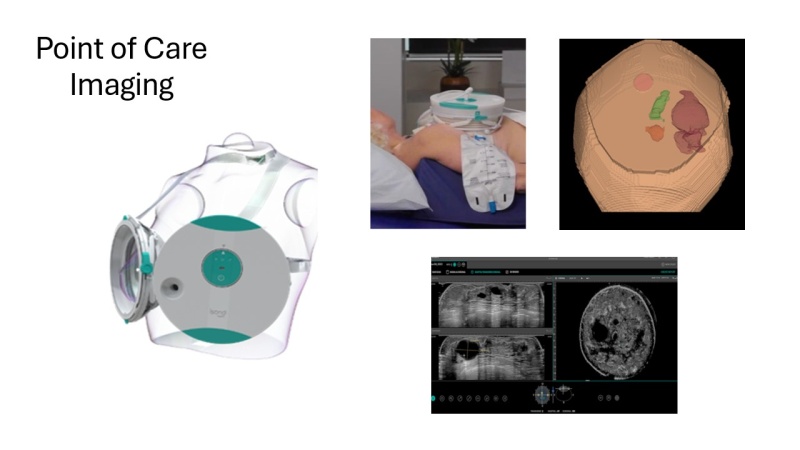

A newly awarded five-year, $4 million grant from the U.S. National Cancer Institute supports a partnership between Vanderbilt University Medical Center and the Uganda Cancer Institute (UCI) to optimize, validate, and deploy a portable diagnostic kit for breast cancer that merges innovative point-of-care technologies in ultrasound and cytology. The goal is for the kit to be used at community health centers that provide outpatient care in sparsely populated areas.